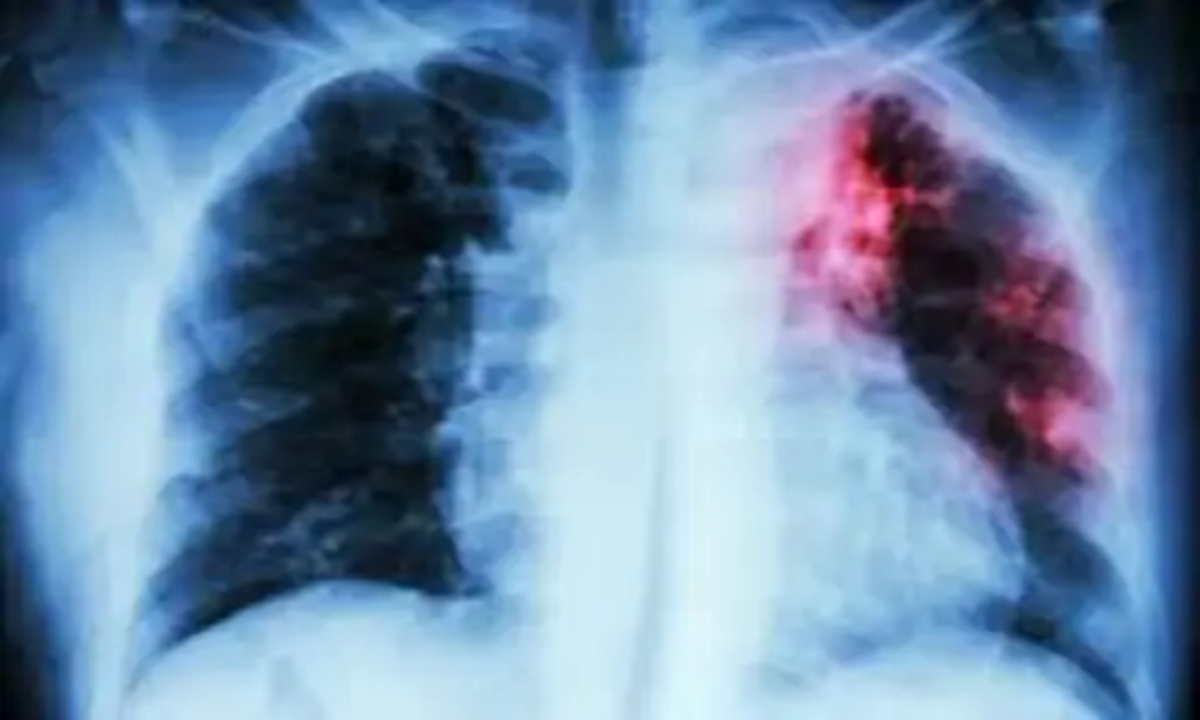

एक्स-रे जांच की स्थिति और भी चिंताजनक है। सरकारी अस्पतालों में 28 लाख से अधिक मरीजों को टीबी के संदेह में एक्स-रे जांच के लिए चुना गया, लेकिन इनमें से सिर्फ 8 लाख की ही जांच हो सकी।

रायपुर जैसे संसाधन संपन्न जिले में भी केवल 41 प्रतिशत संदिग्धों की ही एक्स-रे जांच की गई है। कई सामुदायिक स्वास्थ्य केंद्रों और पीएचसी में एक्स-रे मशीनें खराब रहती हैं या फिल्म की कमी बनी रहती है, जिससे जांच प्रभावित हो रही है।